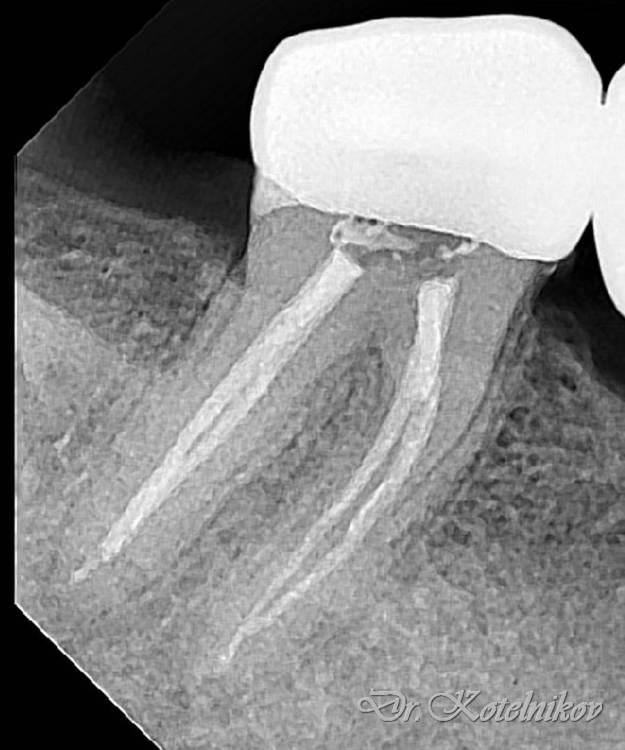

Ico Опубликовано 10 апреля, 2022 Автор Поделиться Опубликовано 10 апреля, 2022 (изменено) 3 отдельных канала в нижнем премоляре,паковка похожая как у Томаса Ланга.Каллибровка,паковка апексов была по S2 протейперу + 25 к. Изменено 10 апреля, 2022 пользователем Ico 1 1 2 Ссылка на комментарий